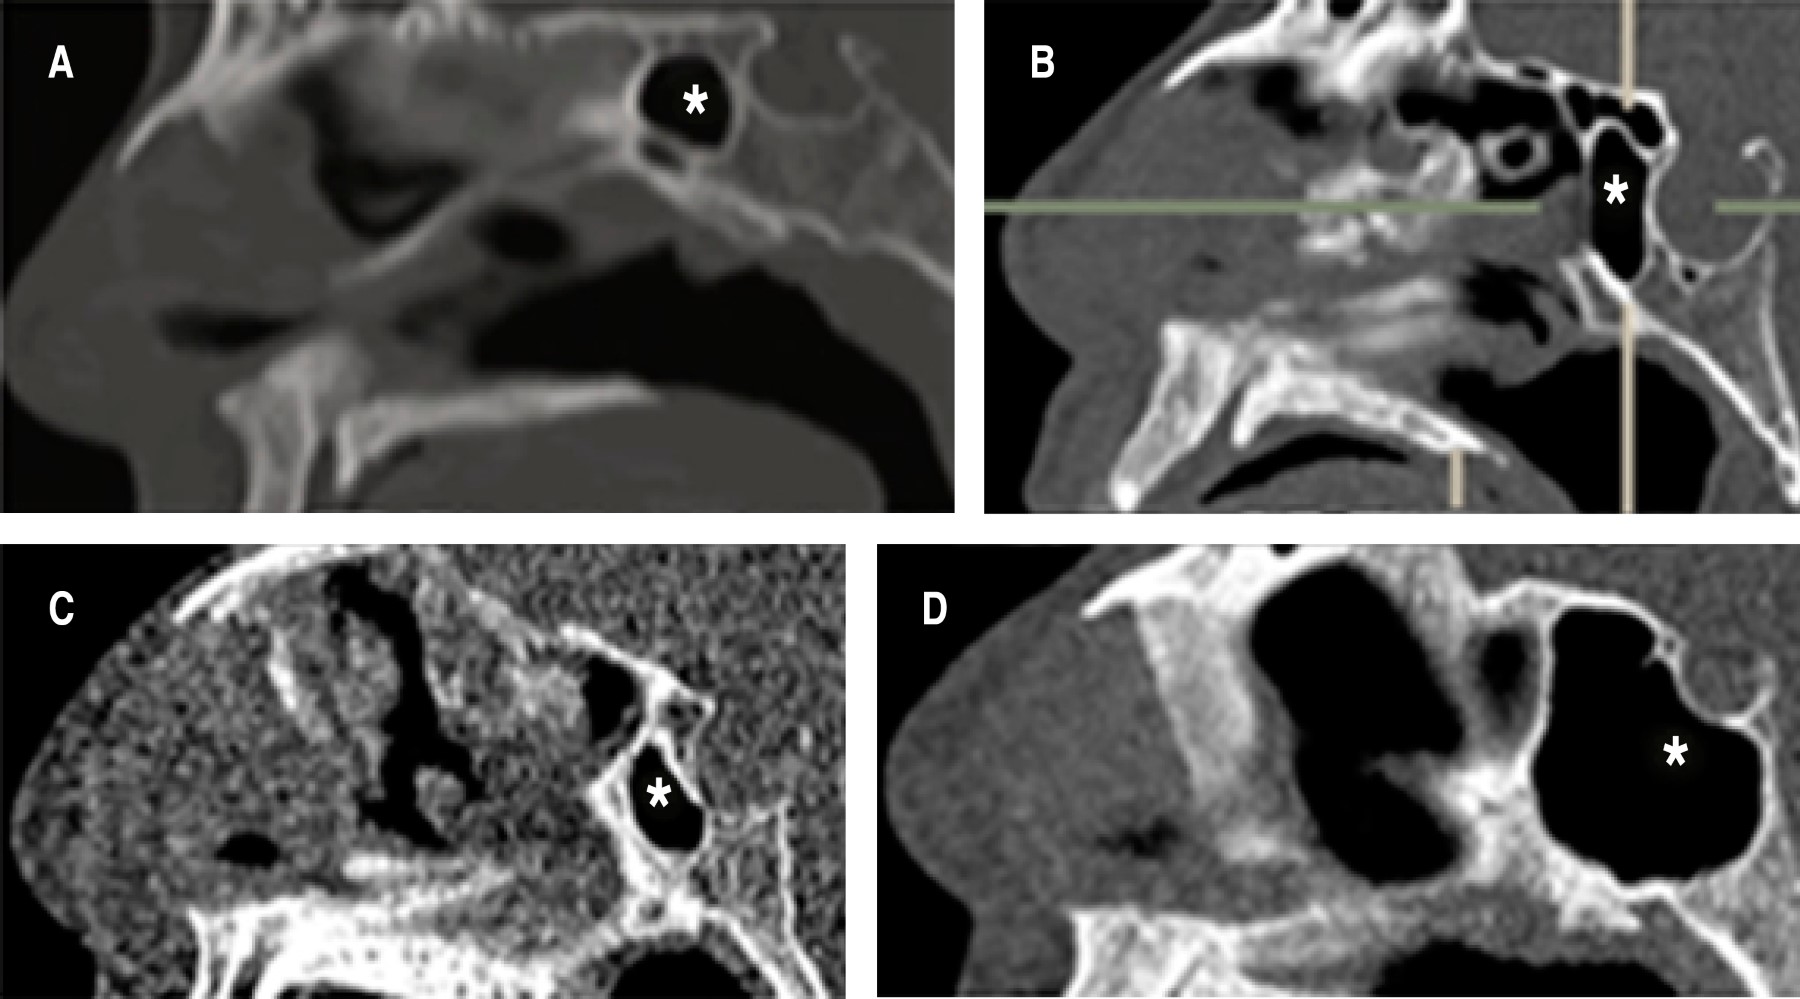

Basado en la extensión de la neumatización, el seno esfenoidal puede clasificarse en: tipo conchal, el seno esfenoidal es un espacio pequeño enfrente de la pared anterior de la silla turca. Tipo presellar, el seno esfenoidal se encuentra en relación a la pared anterior, la pared posterior del seno esfenoidal se localiza enfrente de la pared posterior de la silla turca. Tipo sellar, la pared posterior del seno esfenoidal está localizada entre la pared anterior y posterior de la silla turca. Tipo postsellar: la pared posterior del seno esfenoidal se localiza posterior a la pared de la silla turca (Figura 1).5,6

Según la clasificación de Delano, se puede hablar de cuatro variantes del trayecto del nervio óptico en cuanto a su relación con los senos paranasales. Tipo I, el nervio óptico cursa inmediatamente adyacente al seno esfenoidal pero sin tener contacto con las celdillas etmoidales posteriores, ni indentar la pared. Tipo II, cursa adyacente al seno esfenoidal causando la indentación de la pared del seno. Tipo III, atraviesa el seno esfenoidal y es rodeado en al menos 50% por aire. Tipo IV, está en contacto directo con el seno esfenoidal y con las celdillas etmoidales posteriores (Figura 2).1

Figura 1

Figura 2